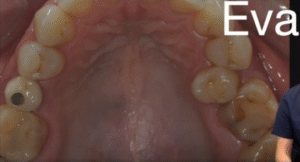

IL PROBLEMA DI EVA: UN DENTE FUORI POSTO E TRE MORSI INCROCIATI

Eva, 46 anni, non era felice del suo sorriso.

Uno dei suoi premolari era scivolato verso il palato, nascosto dietro agli altri denti.

Quel dente “fuori posto” stava creando:

⚖️ Tre morsi incrociati (cross bite): la parte superiore e quella inferiore non combaciavano più.

🍽️ Masticazione difficile: alcuni cibi erano scomodi da masticare, altri quasi impossibili.

🪞 Un sorriso asimmetrico, che lei cercava di nascondere nelle foto.

😬 Sforzo muscolare e tensione mandibolare, con fastidio alle articolazioni.